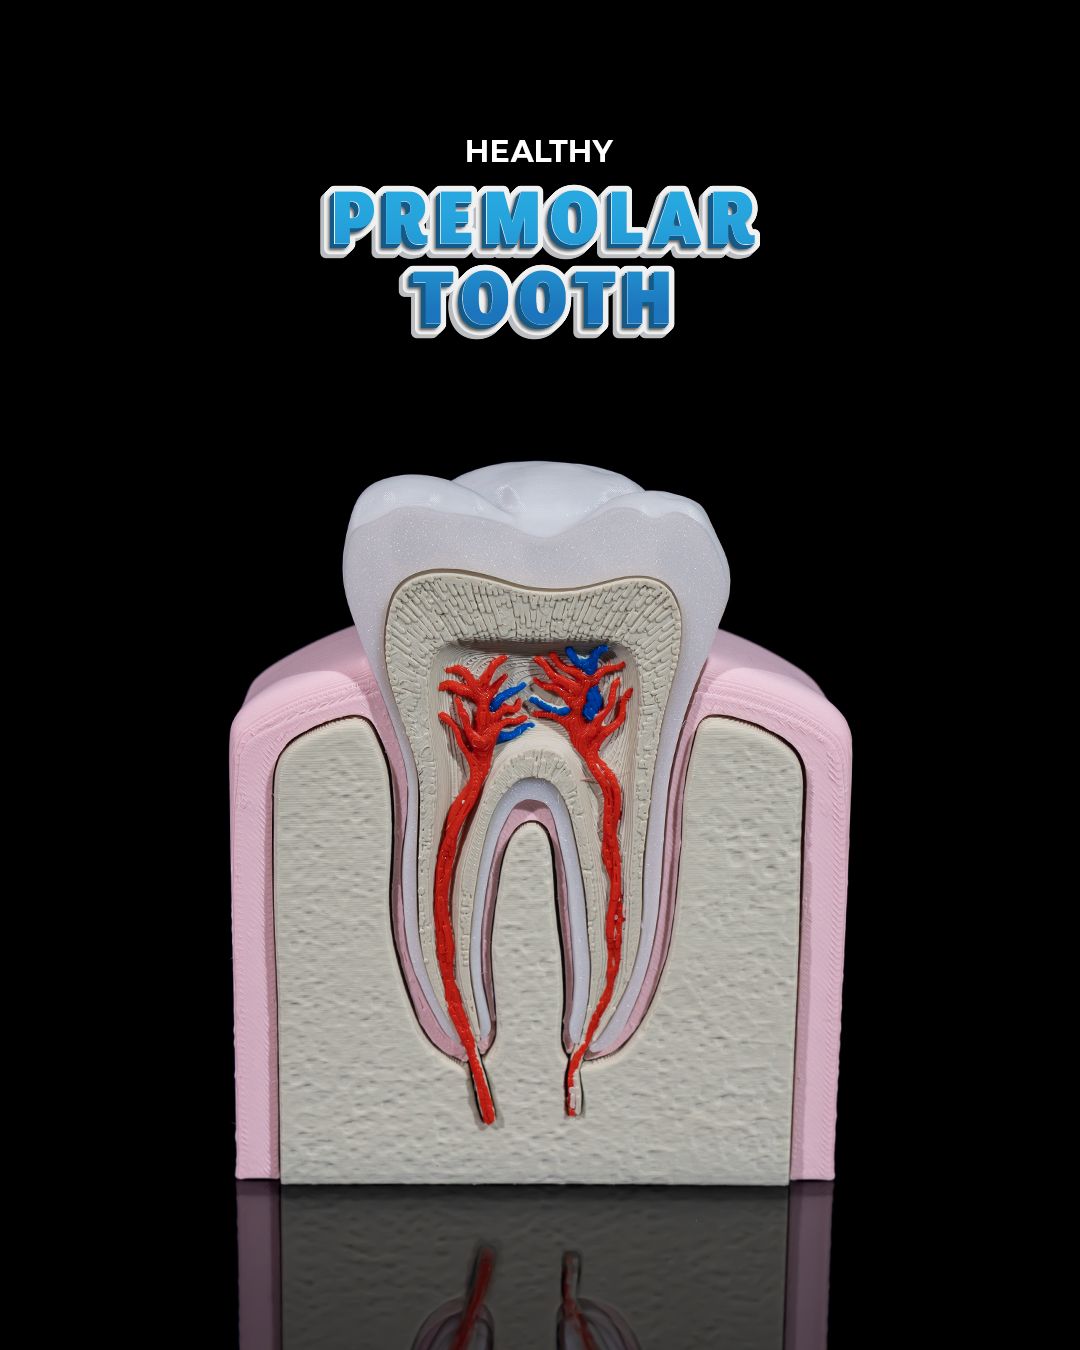

🦷 3D Printed Healthy Premolar Tooth – Precision You Can Smile About

Perfect for dental education, display, or interactive learning, this anatomically accurate premolar model showcases the structure and strength of a healthy adult tooth. It’s a striking blend of science and craftsmanship, ideal for classrooms, clinics, and curious minds.

- True-to-life size and shape for tactile exploration

- Clearly defined cusps, root formation, and enamel contours

- Excellent for explaining oral hygiene, dental anatomy, and procedures